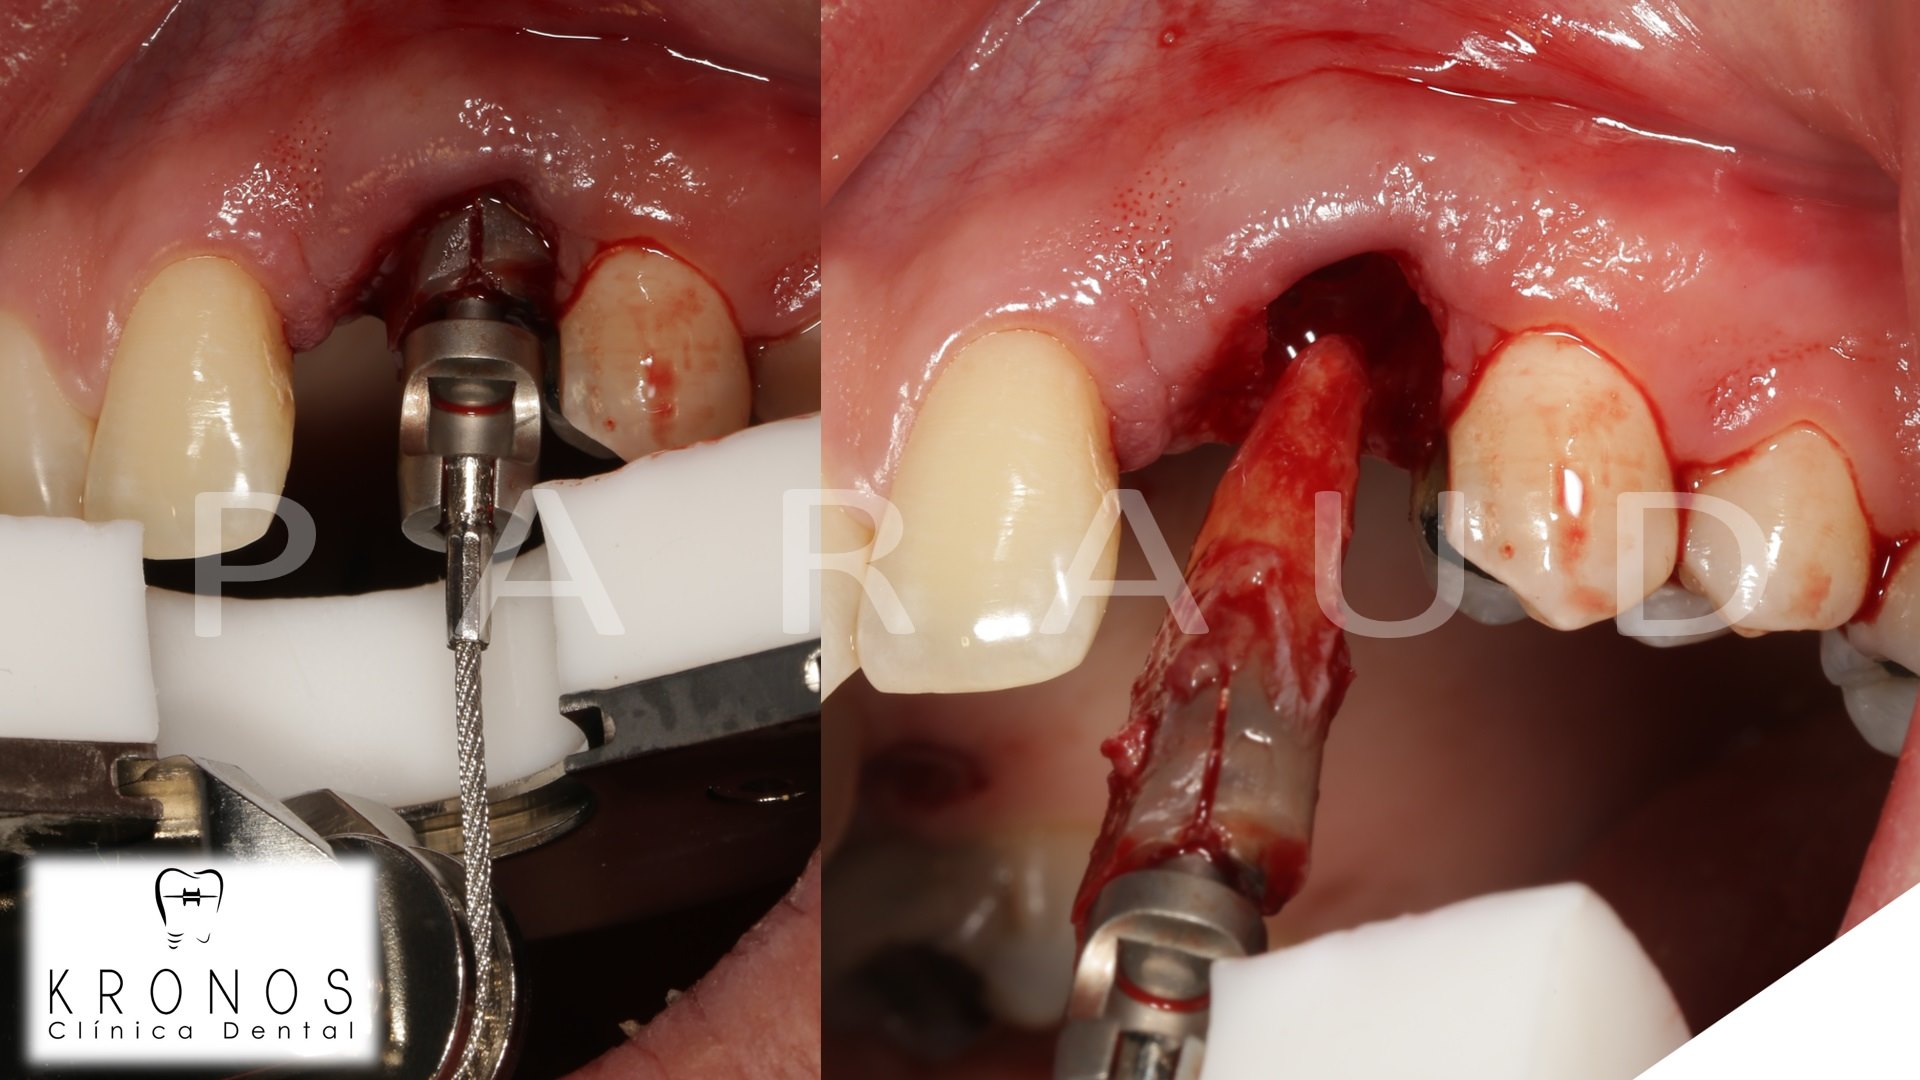

Clinical case: AnyRidge immediate loading

- Courtesy of Dr. Andres Paraud Freixas, Chile -

AnyRidge, ISQ value, initial stability, immediate loading, KnifeThread, maxillary anterior, Mega ISQ, Dr. Andres Paraud Freixas

AnyRidge implant system, Mega ISQ, Digital prosthesis

“Patient’s smile was recovered on the day of surgery

with reliable & highly-aesthetic results using AnyRidge & R2GATE. ”